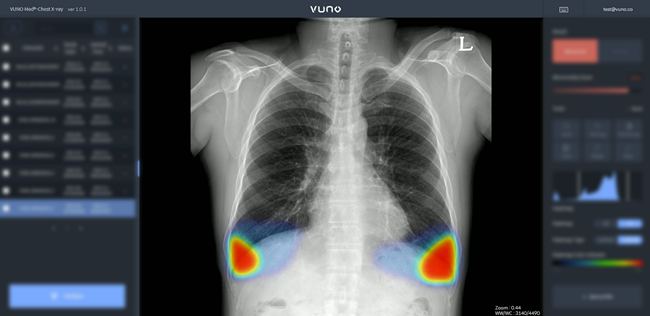

뷰노메드는 '뷰노메드 체스트 엑스레이'가 서울아산병원 건강증진센터에 도입, 활용되고 있다고 밝혔다. (사진. 뷰노메드)

뷰노메드 체스트 엑스레이™는 ▷결절 ▷경화 ▷기흉 ▷삼출 ▷간질성 음영 등 주요 흉부 촬영 영상 의 이상소견을 탐지하고, 병변 부위를 정확히 제시해 의료진 판독을 돕는 인공지능 솔루션이다. 임상시험을 통해 5가지 흉부 이상 소견에 대한 높은 성능(AUROC)과 함께 우수한 민감도와 특이도를 입증해, 지난 2019년 8월 식품의약품안전처 허가를 받았다. 해당 솔루션은 코로나19로 인한 폐렴 진단에도 도움을 줄 수 있어, 국내 수도권 및 강원도와 충청 지역 선별진료소, 대구·경북 내 대형 병원 등에서 영상의학적 폐렴 여부 신속 확인 등 코로나19 대응에도 활발하게 활용되고 있다.